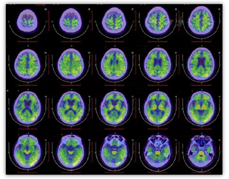

MRI示双侧额叶及颞叶脑沟加深,皮层变薄,以右侧更著。18F-FDG显像示:大脑皮层显像剂分布较普遍稀疏,以双侧额叶内侧皮质、前扣带回及颞叶为著(右侧更明显)(图2)。

淀粉样蛋白PET成像:11C-PIB显像示大脑皮层PIB浓聚程度增高,以左侧顶枕颞叶更明显,提示淀粉样斑块沉积(图3)。